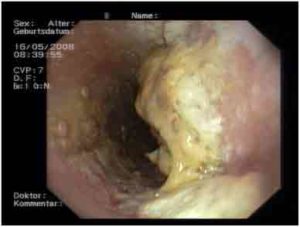

Молочница пищевода характеризуется воспалительным процессом. Пациенты начинают отмечать трудности при глотании, а также часто испытывают боли за грудиной после еды. В некоторых случаях может возникать рвота. Данная форма молочницы нередко путается с опухолевыми образованиями или стенозом, поэтому крайне важно провести тщательную диагностику. Во время эзофагоскопии врач обращает внимание на наличие белесой пленки и творожистого налета на слизистой оболочке пищевода.

Если удалить такой налет, на слизистой остаются эрозии. При запущенных формах молочницы могут быть затронуты и более глубокие слои тканей, выстилающих пищевод. В таких ситуациях при отрыве налета могут возникать серьезные кровотечения, которые могут длительное время не прекращаться. Кроме того, врач берет образец ткани для дальнейшего исследования, что помогает определить наиболее подходящий план лечения.